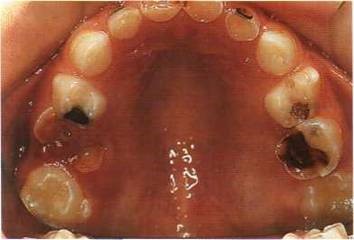

- Одна из основных — невылеченный вовремя кариес, при котором инфекция распространяется глубже и проникает на пульпу зуба.

- Также стремительному распространению воспалительного процесса в молочных зубах способствуют более рыхлая соединительная ткань, более широкие, в сравнении с постоянными зубами, корневые каналы и слабо минерализованный дентин.

Пульпит молочных зубов является распространенной проблемой у детей, и врачи выделяют несколько основных причин его возникновения. Чаще всего это связано с глубоким кариесом, травмами зубов или недостаточной гигиеной полости рта. Симптомы пульпита могут варьироваться от острого болевого синдрома до отека десен и изменения цвета зуба. Врачи подчеркивают важность ранней диагностики, так как запущенные случаи могут привести к серьезным осложнениям, включая потерю зуба.